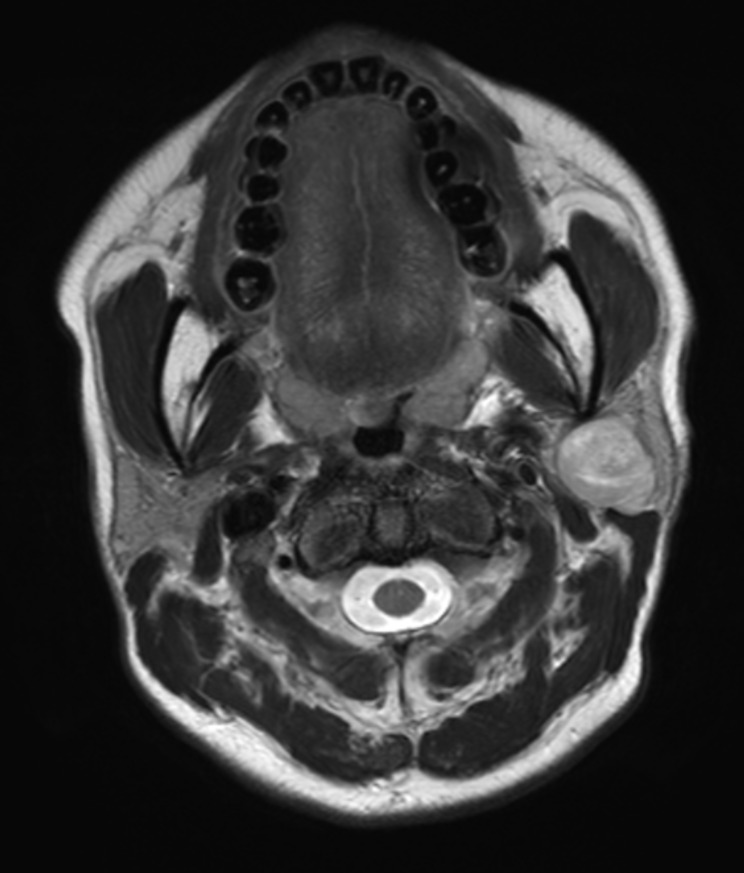

Backgrounds: Preoperative imaging, particularly with magnetic resonance imaging (MRI) and computed tomography (CT) scans, plays a crucial role in distinguishing between benign and malignant parotid gland tumors, while the reliability of Ultrasound-Guided Fine Needle Aspiration (FNA) in diagnosing these masses remains a topic of debate.

Methods: This two-center retrospective analysis was conducted on 347 patients with parotid gland tumors who had FNA and preoperative imaging (CT or MRI). All patients underwent surgery and final histopathological examination was available, along with complete medical records between January 2008 and May 2023.

Results: Among the 347 patients, 318 (92%) had benign and 10 (3%) had malignant tumors based on FNA, with 19 (5%) unsatisfactory specimens. Final histological diagnosis revealed 303 (87%) benign and 44 (13%) malignant lesions, with a false-negative rate of 10.6% for FNA. Multivariate analysis identified irregular shape and invasion as independent predictors of malignancy in patient with benign or unsatisfactory FNA results. The odds ratio for irregular shape was 3.06 and for invasion was 12.73.

Conclusion: Imaging characteristics, such as irregular shape and invasion may indicate towards malignant parotid tumors, even in patients with false-negative benign findings in FNA.